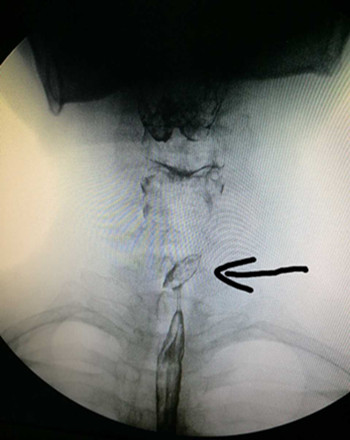

患者來我院就診時,咽痛嚴重,飲水時有哽噎感,4天來未進飲食,身體非常虛弱。遂抱著試一試的心態來到我院耳鼻咽喉科門診就診,張立剛副主任看過患者后經過綜合評定,認為我院已具備此例手術條件,門診遂以“食管異物”收住入院。入院后張立剛副主任立即組織安排手術前相關檢查事項,急查上消化道造影提示:食道(約第3胸椎水平)可見一橢圓形異物。尚規劃主治醫生立即給予積極完善相關檢查、補液、消腫,待患者基礎情況好轉,能耐受手術后,急診在全身麻醉下行食管內異物取除術,用硬質食管鏡直視下發現棗核兩端還是橫向扎在食道壁,此處離主動脈弓只有不到2cm,稍有不慎即可損傷主動脈造成無法控制的大出血,或者引起食道穿孔,與術前評估情況沒有差異。張立剛副主任沉著冷靜,尚規劃醫生一絲不茍,在兩人默契配合下,順利將棗核取出。術后患者在耳鼻咽喉科醫護團隊的細心治療與護理下于迅速康復出院。此例經硬質食道鏡成功取異物病例填補了我院硬質食道鏡取除食道異物的空白。